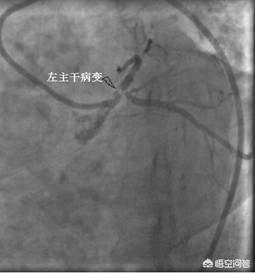

①Diagnostic clair.Le diagnostic de la maladie coronarienne n'est pas difficile à établir avec le niveau actuel des soins médicaux.coronarographieUn diagnostic définitif de la maladie coronarienne peut être posé. Un cathéter est introduit dans les artères directement jusqu'aux artères coronaires, puis un produit de contraste est libéré pour visualiser les artères coronaires, ce qui donne une image claire de l'emplacement et de l'étendue de l'obstruction, et fournit une base pour le traitement ultérieur. C'est pourquoi il s'agit également du traitement le plus courant de la maladie coronarienne.L'"étalon-or" pour le diagnostic de la maladie coronarienne.。

Bien que les symptômes d'angine de poitrine, l'élévation du taux de troponine et les modifications de l'électrocardiogramme soient utiles au dépistage de la maladie coronarienne, l'étalon-or du diagnostic de la maladie coronarienne est la coronarographie, qui est une procédure invasive mais qui joue un rôle irremplaçable dans le diagnostic de la maladie coronarienne et dans la compréhension de la sévérité de la maladie. Grâce à l'injection d'un produit de contraste, la coronarographie permet d'observer clairement le degré de rétrécissement de l'artère coronaire, et lorsque le rétrécissement de l'artère coronaire atteint 50 %, la maladie coronarienne peut être diagnostiquée. La coronarographie permet également de comprendre les parties malades et la quantité de l'artère coronaire, ce qui peut fournir des indices très précieux pour l'évaluation de l'état de la maladie. Certains d'entre vous se demandent peut-être si la maladie coronarienne peut être guérie. Avec la technologie médicale actuelle, nous ne pouvons pas guérir la maladie coronarienne. Toutefois, le risque de progression vers l'infarctus du myocarde peut être réduit par un traitement rationnel, comprenant l'application de médicaments antiagrégants plaquettaires tels que l'aspirine ou le clopidogrel, l'utilisation de médicaments stabilisant la plaque tels que les statines, etc., ainsi que des médicaments améliorant le pronostic tels que les bêtabloquants et le priligy, etc. la maladie coronarienne.